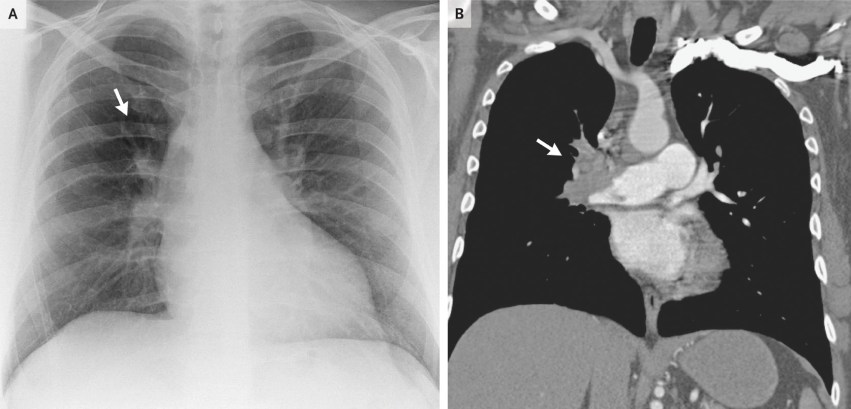

Westermark’s Sign

Definition – focal peripheral hyperlucency resulting from collapsed vessels distal to a pulmonary thromboembolism.

Clinical Significance – Occurs as a result of oligemia of perfusion to the lung parenchyma and can be seen in up to 10% of patients with acute PTE. Similar to Hampton’s Hump, it has a low sensitivity, but a high specificity